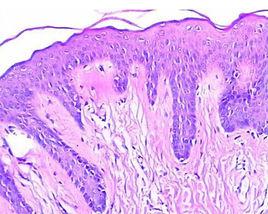

病理診斷是對手術切下或屍體解剖取下之腫瘤標本,固定染色後,在顯微鏡下進行組織學檢查,以診斷疾病,更多的是在活人身上,在治療前,用鉗取、切除或切取方法取得腫瘤組織,固定染色後,在顯微鏡下進行病理診斷。儘管各種影像學技術飛速發展,但是病理診斷仍然是腫瘤各種檢查方法中最可靠的,病理診斷被喻為“金標準”,也是疾病的最終診斷。

病理診斷是在觀測器官的大體(肉眼)改變、鏡下觀察組織結構和細胞病變特徵而做出的疾病診斷,因此它比臨床上根據病史、症狀和體徵等做出的分析性診斷(常有多個診斷或可能性診斷)以及利用各種影像(如超音波、X射線、CT、核磁共振等)所做出的診斷更具有客觀性和準確性。儘管現代分子生物學的診斷方法(如PCR、原位雜交等)已逐步套用於醫學診斷,但到目前為止,病理診斷仍被視為帶有宣判性質的、權威性的診斷。由於病理診斷常通過活體組織檢查(biopsy)或屍體剖檢,來回答臨床醫生不能做出的確切診斷和死亡原因等問題,國外將病理醫生稱之為“doctor’s doctor”。然而,病理診斷也不是絕對權威,更不是萬能的,也和其他學科一樣,有其固有的主、客觀的局限性。因此,提高自身技術水平、臨床-病理醫生相互溝通,對於減少和杜絕漏診、誤診是十分必要的。